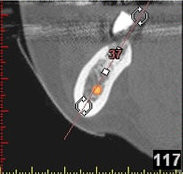

In komplexen Fällen, z. B. der Implantatversorgung eines kompletten Kiefers, oder bei schwierigen Knochensituationen bietet die 3-dimensionale Computerdiagnostik bzw. Planung und Durchführung erhebliche Vorteile und Sicherheit für den Patienten (siehe Bild 1 und 2).

Auf Basis einer computertomografischen (CT-) Kieferaufnahme ist eine dreidimensionale Darstellung der Knochen möglich. Der Zahnarzt kann dann am Computerbildschirm die Knochenqualität (z. B. Knochendichte) beurteilen und die optimale Position der Implantate im Vorfeld planen. Durch Verwendung spezieller Röntgenschablonen lässt sich auch die erwünschte Zahnstellung in die Planung einbeziehen. Die Simulation der OP erlaubt, das zu erwartende Ergebnis mit größtmöglicher Sicherheit vorherzusagen und dem Patienten am Bildschirm zu veranschaulichen.